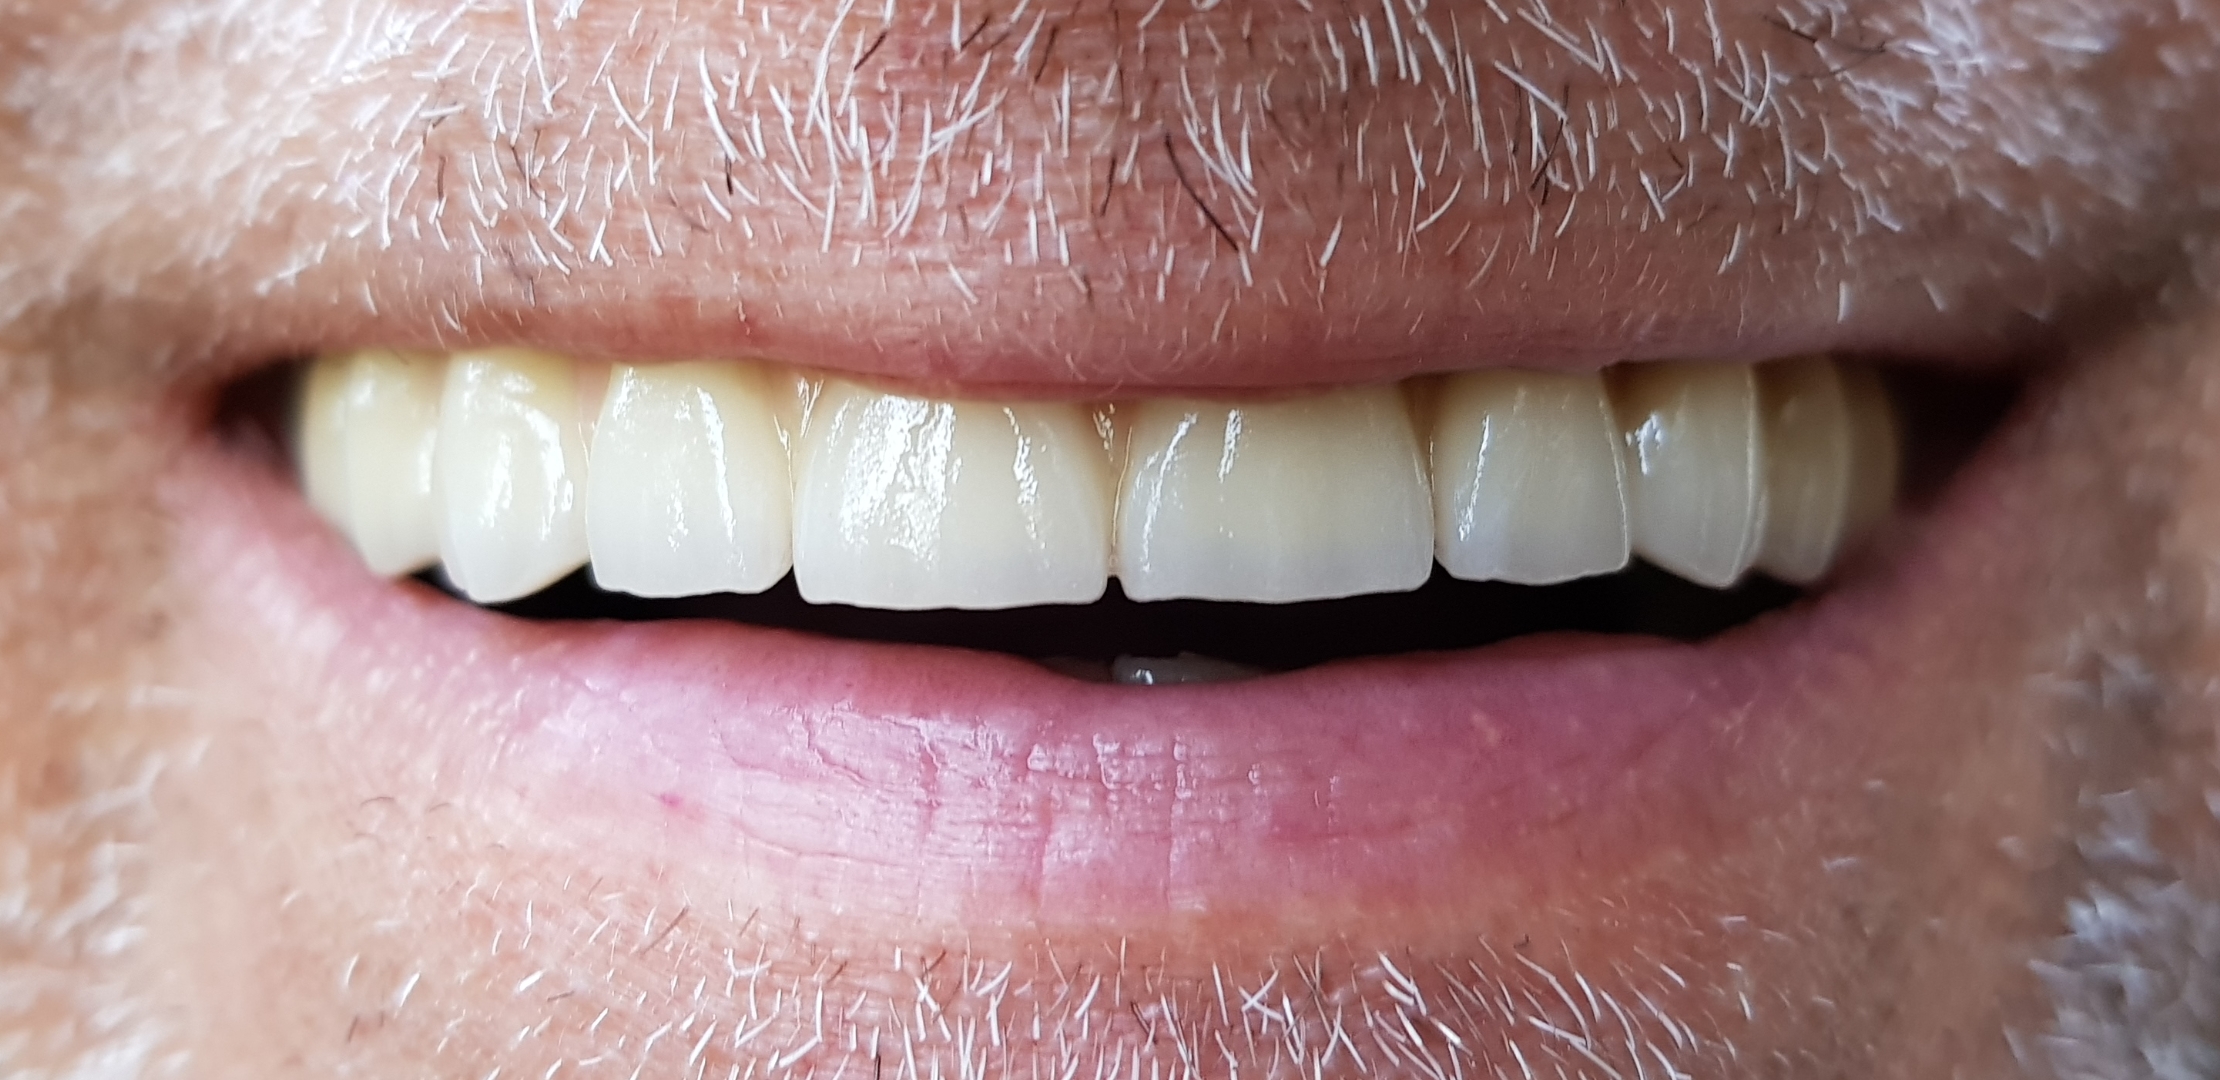

Felső fogatlan állcsont korszerű ellátása: felső teljes fogatlanság kezelése 6 implantátumon rögzített fix híddal. Multi unit tengelykorrekciós fejek, csavarosan rögzített híd.

Implantátum: Nobel Biocare.

Hídpótlás anyaga: cirkónium vázra égetett porcelán.

A választott fogszín: A1.

A protetikai munka elkészülésének ideje: 8 munkanap.